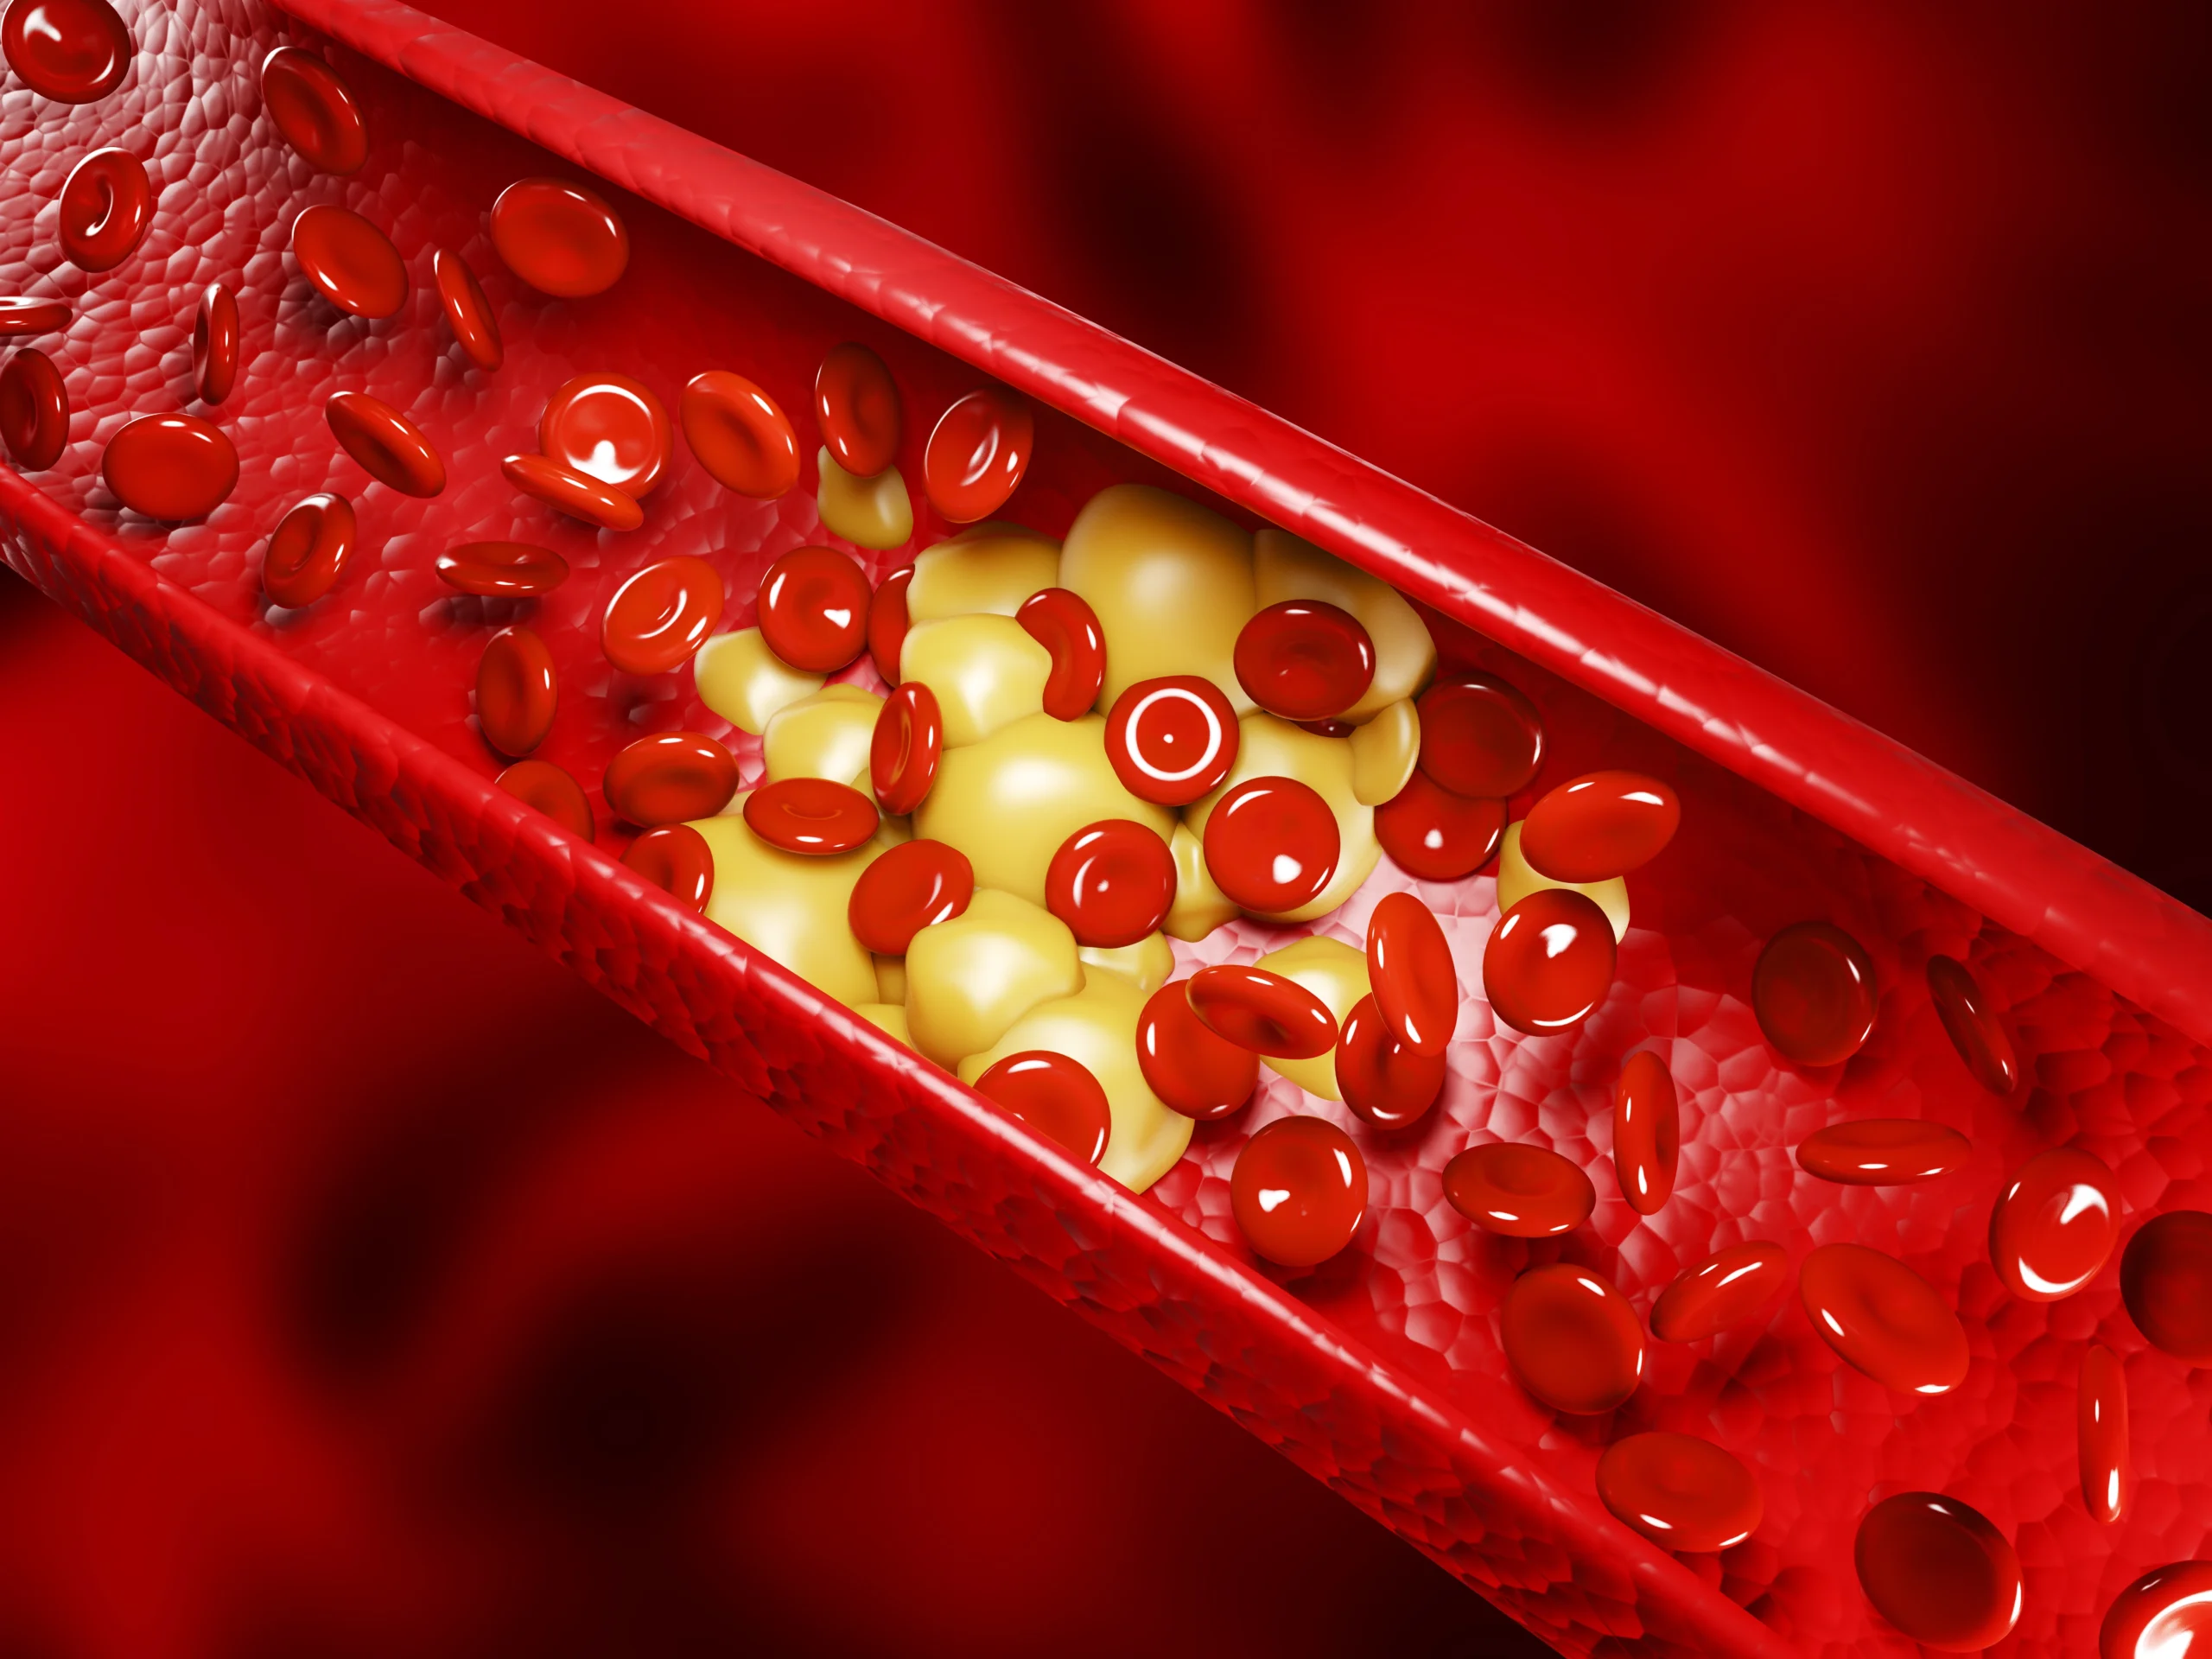

Tekanan ini sering terjadi akibat penyempitan foramen, yaitu saluran kecil di tulang belakang tempat saraf keluar atau sering disebut spinal stenosis.

Spinal stenosis adalah kondisi penyempitan saluran tulang belakang yang dapat memengaruhi sumsum tulang belakang atau saraf yang keluar darinya.

Penyempitan ini biasanya terjadi akibat penuaan, cedera, atau penyakit seperti artritis. Ketika saluran tulang belakang menyempit, maka tekanan pada saraf akan meningkat.

Tekanan ini dapat menyebabkan rasa sakit yang tajam, mati rasa, hingga kelemahan pada bagian tubuh dengan kondisi saraf tersebut.